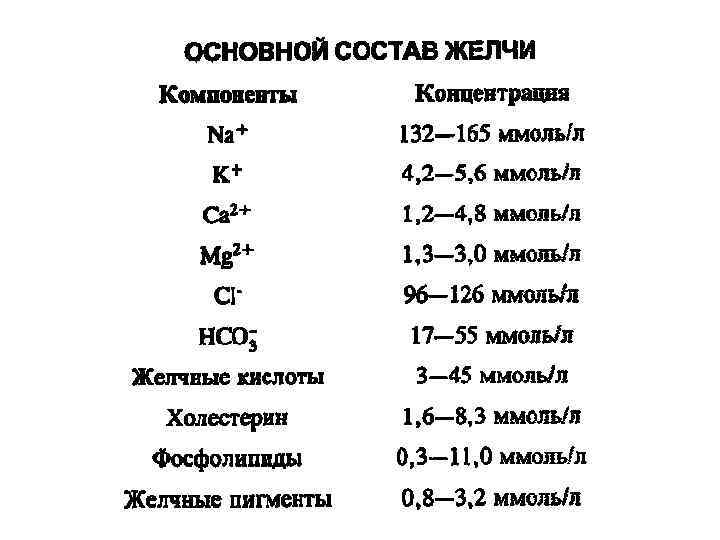

Основные компоненты жёлчи • • • Жёлчные кислоты Электролиты (катионы, анионы) Холестерин Фосфолипиды Жёлчные пигменты

Основные компоненты жёлчи • • • Жёлчные кислоты Электролиты (катионы, анионы) Холестерин Фосфолипиды Жёлчные пигменты